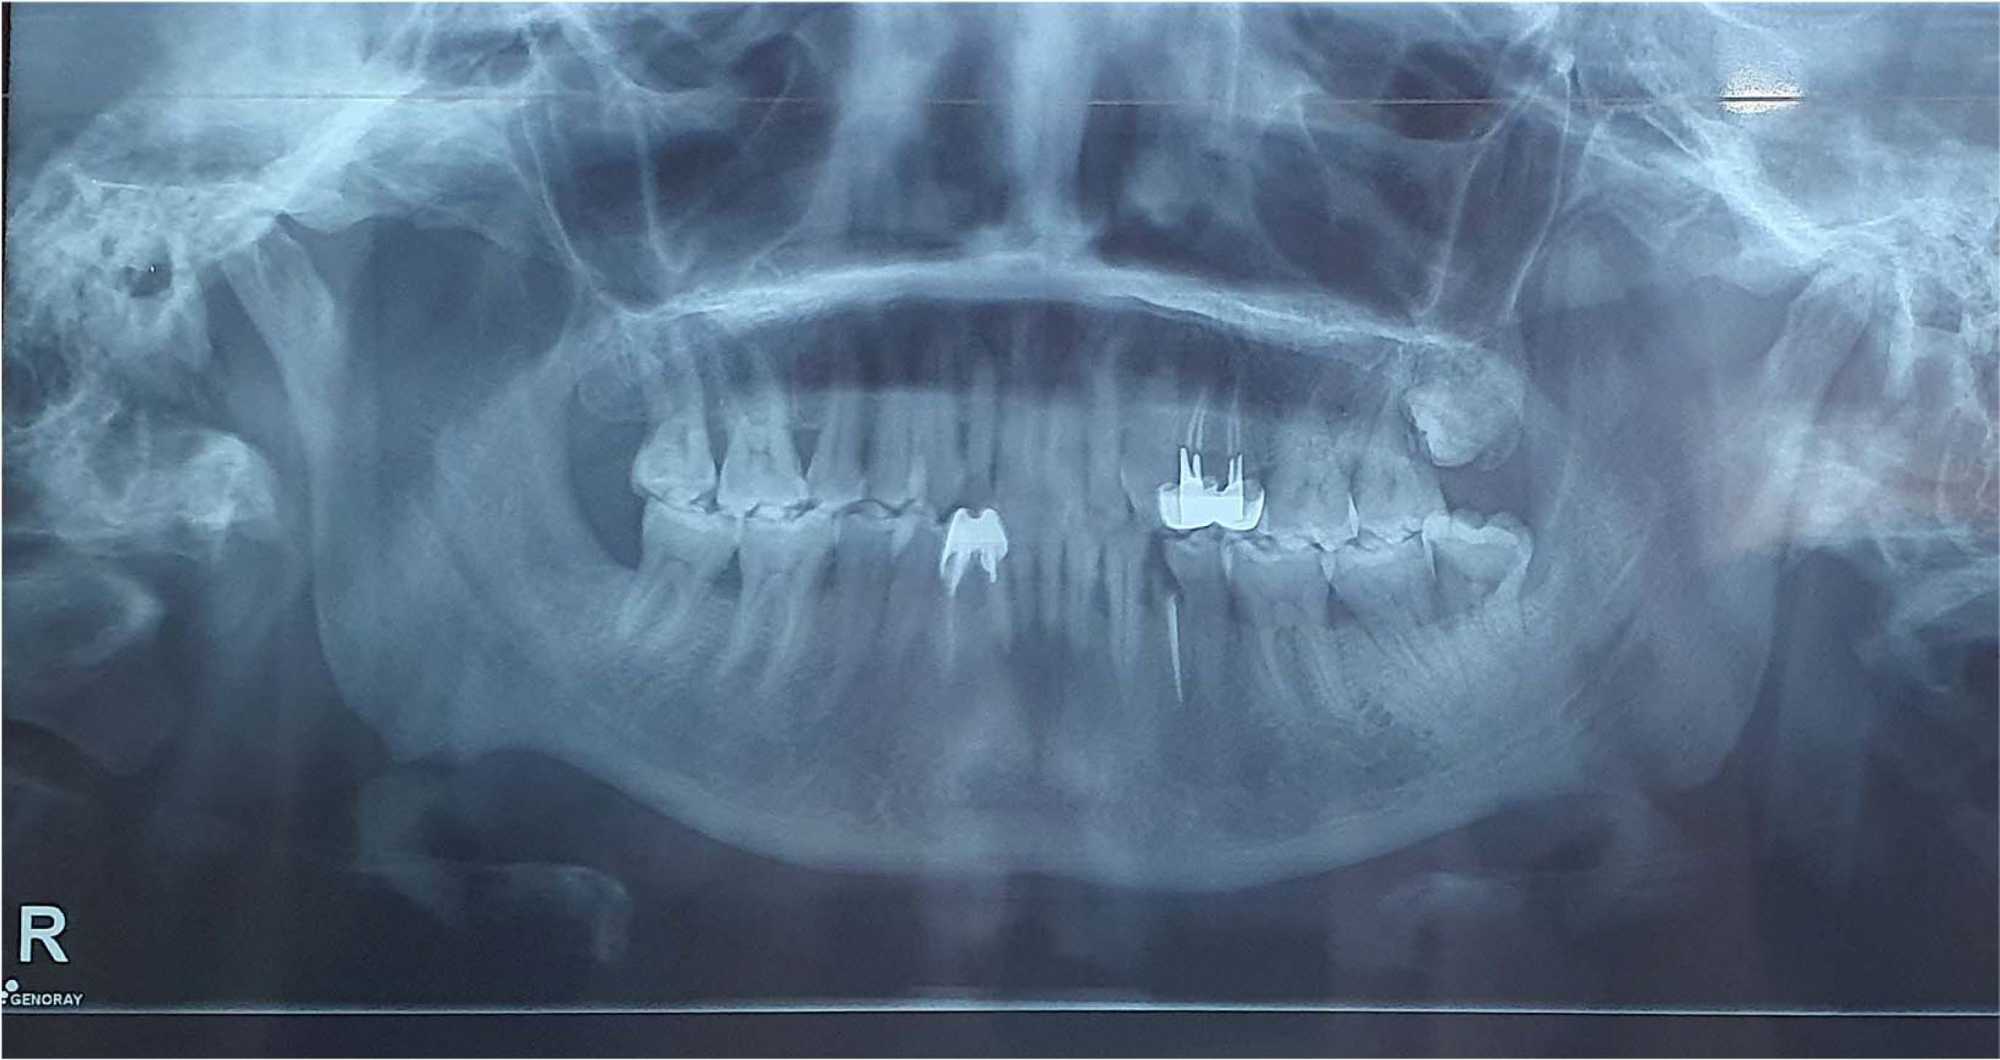

A panoramic radiograph showed contact between the mental foramen and the site of tooth 35 (Figure 4).

Figure 4. Panoramic radiograph: contact of the site of extraction of tooth 35 with the mental foramen.

A panoramic radiograph confirmed the absence of tooth 48 and showed evidence of bone healing (Figure 6).

Figure 6. Panoramic radiograph: Absence of tooth 48 with signs of healing bone.